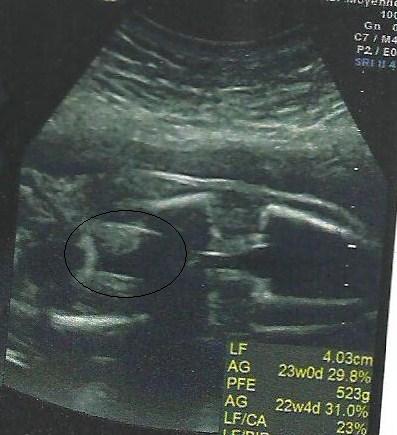

I've no idea what I'm looking at?

you're looking at bit of pelvis , femur , knees and tibias lol

but what is that other thing ?

Bladder in focus and genital area shown but not in focus xx

Could be a dangly there though...